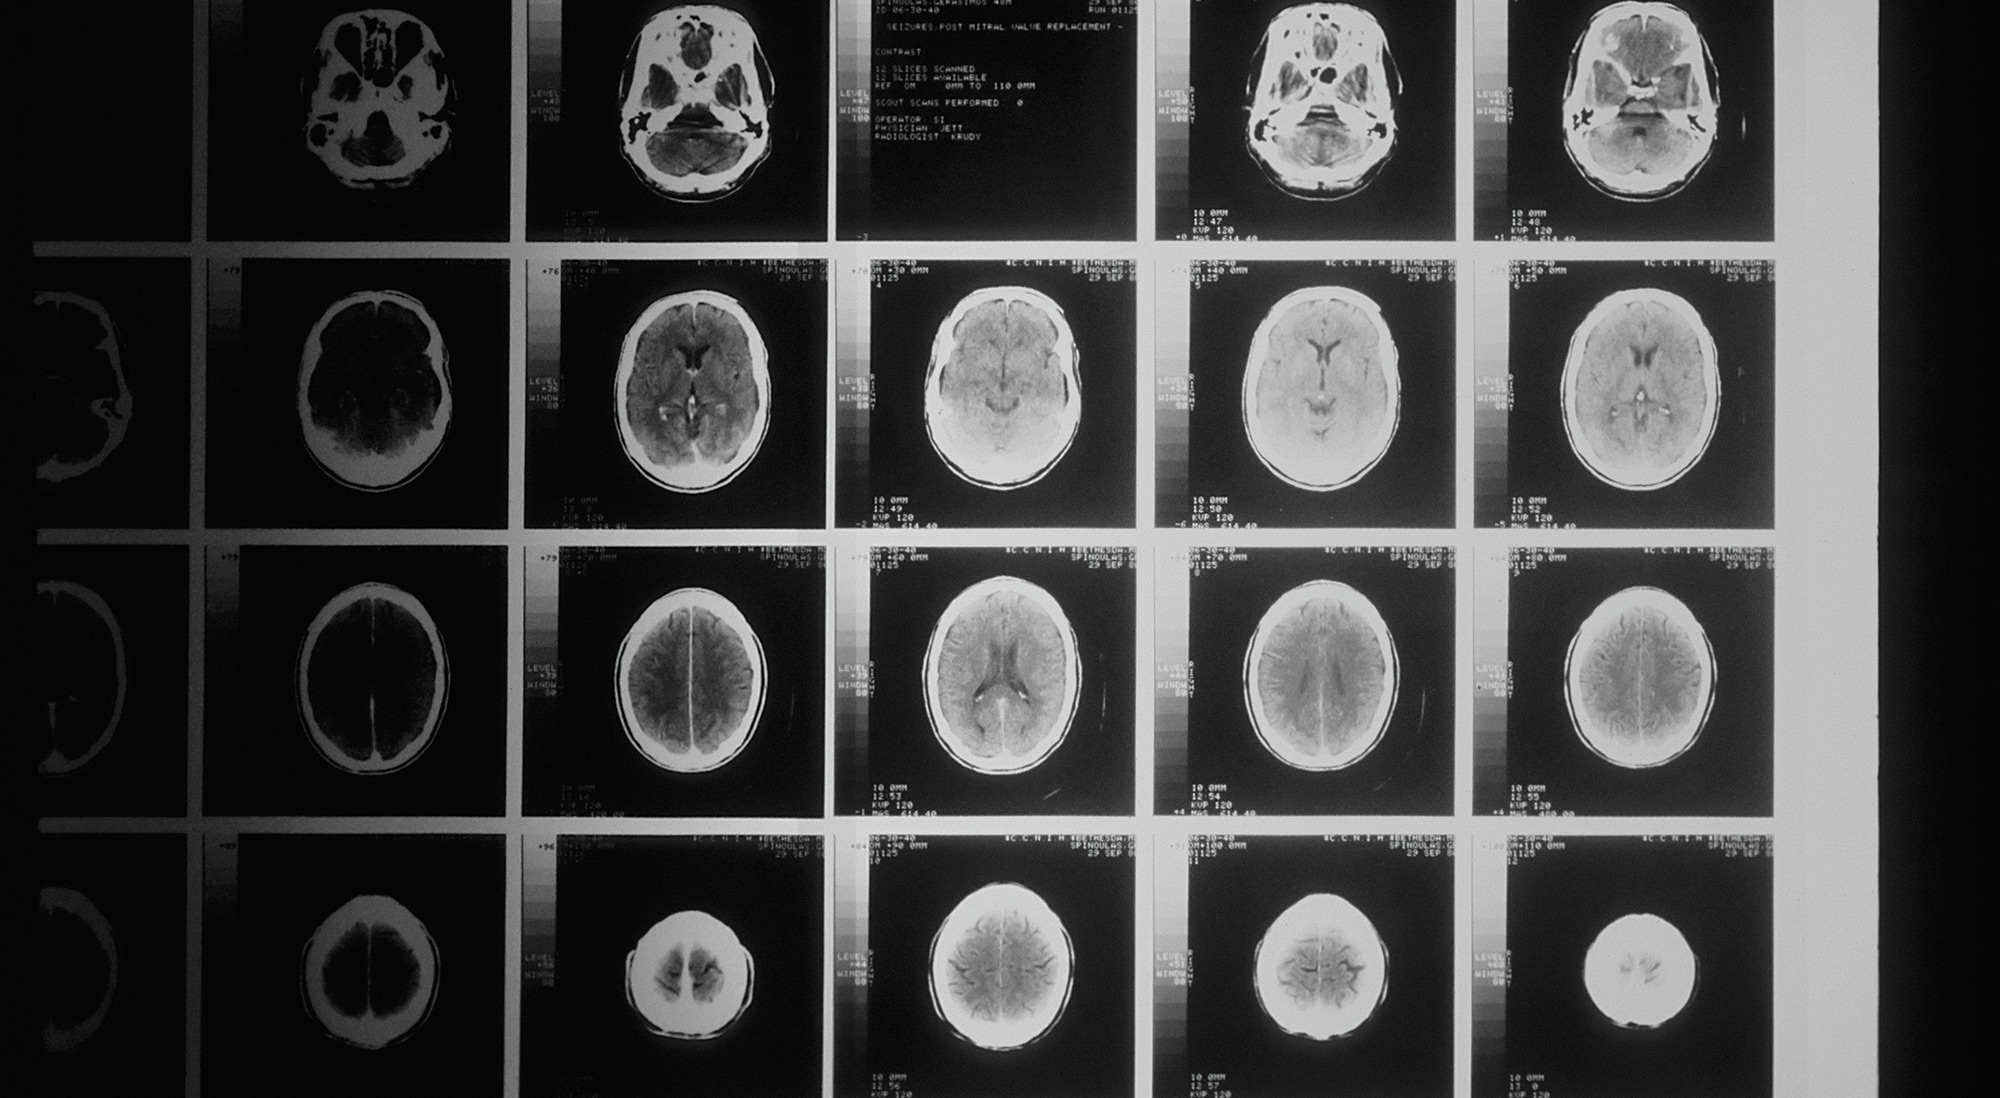

Las lesiones cerebrales traumáticas pueden estar provocadas por un golpe en la cabeza o por la penetración de un objeto en el cráneo. Pueden afectar a la capacidad de pensar de una persona, así como a sus funciones motoras y emocionales. Prácticamente cualquier tipo de accidente puede provocar una lesión cerebral, y la gravedad de estas lesiones puede, en ocasiones, dar lugar a una discapacidad prolongada o incluso permanente, lo que conlleva gastos médicos, pérdida de salarios y pérdida de ingresos futuros.

Cualquier lesión o golpe en el cráneo puede provocar daño cerebral, e incluso otros tipos de lesiones pueden interrumpir el riego sanguíneo al cerebro y causar daños. Si usted o un ser querido ha sufrido un accidente, es importante que un profesional médico le examine lo antes posible para detectar posibles lesiones cerebrales, ya que ciertos tipos de daño cerebral pueden empeorar si no se tratan a tiempo. Si le diagnostican una lesión cerebral, nuestros abogados pueden ayudarle a buscar asistencia médica y una indemnización en Long Island.